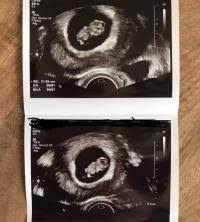

5 2 ssw ultraschall. WocheHabe Angst das sich ein Windei eingenistet hat weil man nur die leere Fruchthöle sieht. Auf diesem Bild kann man nun beides sehen.

Das ist jedoch erst mal kein Grund zur Beunruhigung. Nein noch nicht. Aber für 52 ist das ja nicht schlimm.

Ich denke zu diesem Zeitpunkt kann mann eh nichts machen. Das ist zu sehen Schwarzsehen war noch nie so schön.